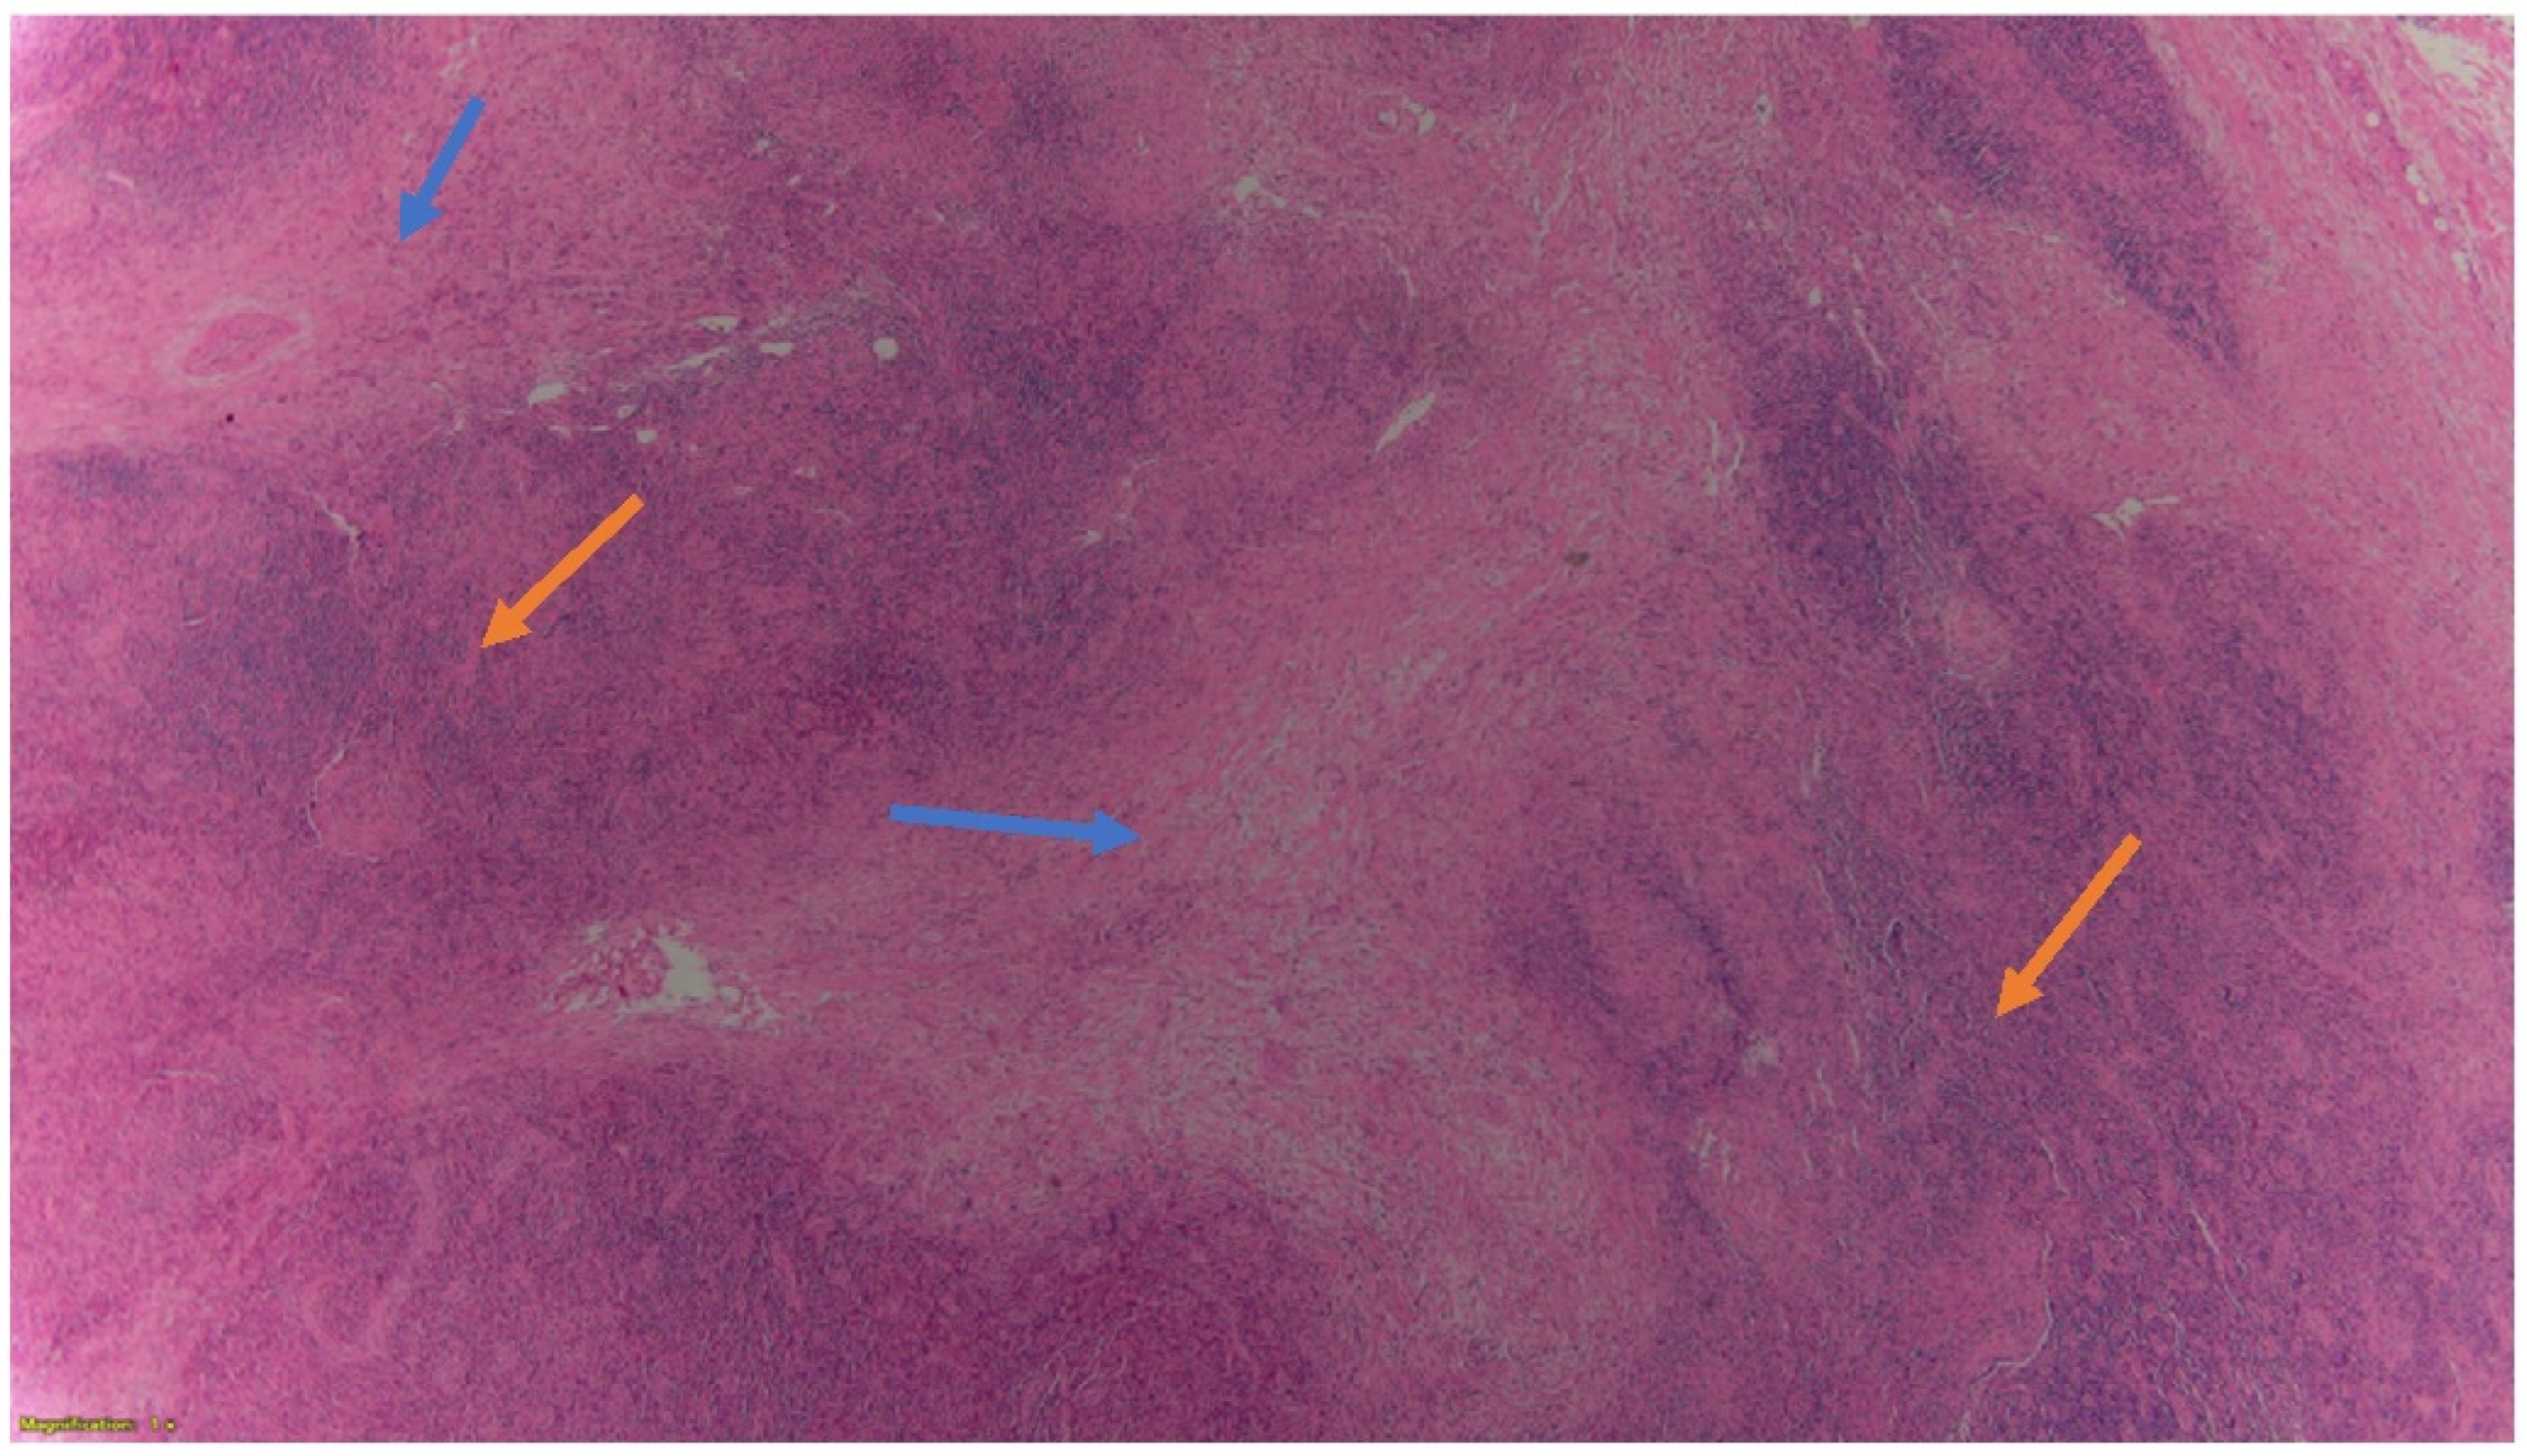

2. Case Presentation